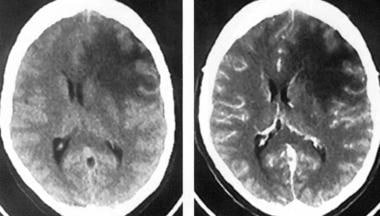

弥漫性脑干胶质瘤占58-75%在全部脑干肿瘤中,典型地发生在脑桥,并且在核磁共振成像上没有被描绘。它们通常是恶性纤维星形细胞瘤(国际卫生组织三级或四级),沿白质束浸润到中脑和丘脑,病程进展迅速并致命。

这些肿瘤的临床表现通常包括共济失调、小脑体征和长束体征。当临床和影像学证据表明弥漫性脑干胶质瘤时,活检的用途有限,因为肿瘤组织学通常不会改变治疗。

没有任何治疗方法可以治愈或延长这些患者的生存期,放射坏死和化疗的副作用可能很大。手术切除的益处尚未显示,主要是由于该区域的口才以及肿瘤的扩散和侵袭性。皮质类固醇可以通过减轻水肿提供暂时的益处。

辐射已被证明可提供暂时的临床好转,有时会被采用,但一项大型三期试验显示无益处。即使采用放射疗法,1年生存率也显示为35-46%,3年生存率为11-17%。